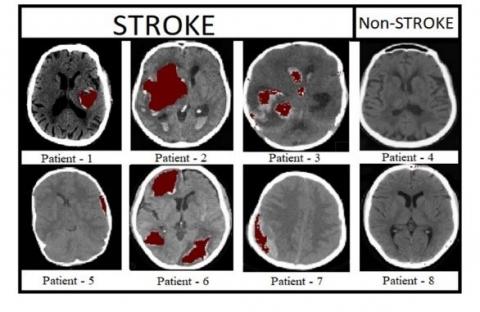

Figure 9 shows the pre-processed brain CT images of 8 patients, in which 6 patients are affected with stroke and remaining 2 are non-stroke patients. Figure 10 shows the labeled brain CT images of 8 patients. These labeled images contain three classes represented with white, gray, and black colors. Patients 4&8 are not affected with stroke, so these images are labeled with only two classes. The images shown in Figure 11 are predicted by our proposed model. Figure 12 shows output images of our proposed stroke segmentation on brain CT images.

Figure 9. Original images of stroke and non-stroke patients